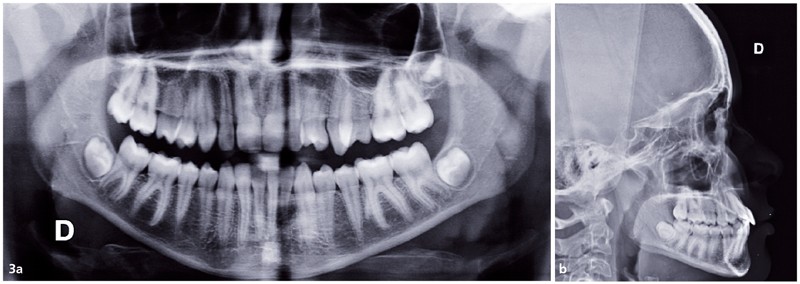

Paulo D., 13 ans, consulte pour un motif esthétique. Il présente une ligne du sourire non harmonieuse, avec la rotation de 24 en place de 23, un sourire gingival à droite et les milieux incisifs non alignés entre eux (fig. 1).

Au niveau squelettique, il présente une classe I tendance classe III (AoBo= -3,5mm) sur un schéma facial normodivergent.

Sur le plan occlusal et dentaire, on observe une classe III molaire et canine à gauche, une proalvéolie maxillaire, une occlusion inversée au niveau des 15/46 et 25/35-36, une non concordance des milieux incisifs et une transposition complète de 23 et 24 (fig. 2 et 3).